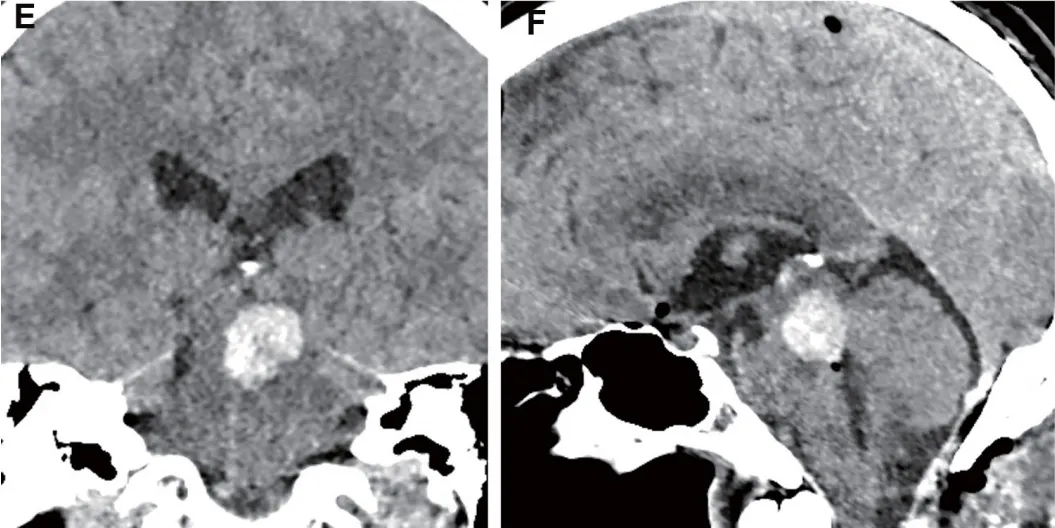

手术团队成功完成主病灶切除,卫星病灶按预定方案予以保留。术后第一天常规头部CT检查发现切除腔内有血肿形成,冠状位和矢状位重建图像清晰显示血肿产生占位效应,并对中脑结构形成压迫。医疗团队立即进行二次手术干预,通过原手术切口清除血肿并彻底止血。患者在神经外科重症监护室接受全面监护,使用多模态监测系统持续追踪生命体征和神经功能变化。